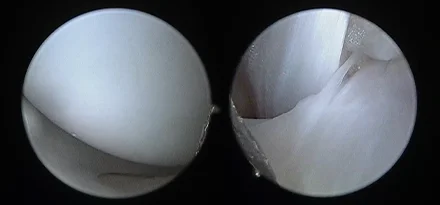

관절경 팔꿈치관절(Elbow) 확인

관절경 무릎관절(Stifle) 확인 (반월판 및 십자인대)

* 리본동물의료센터 케이스 사진으로 무단 복제 및 도용을 금지합니다.